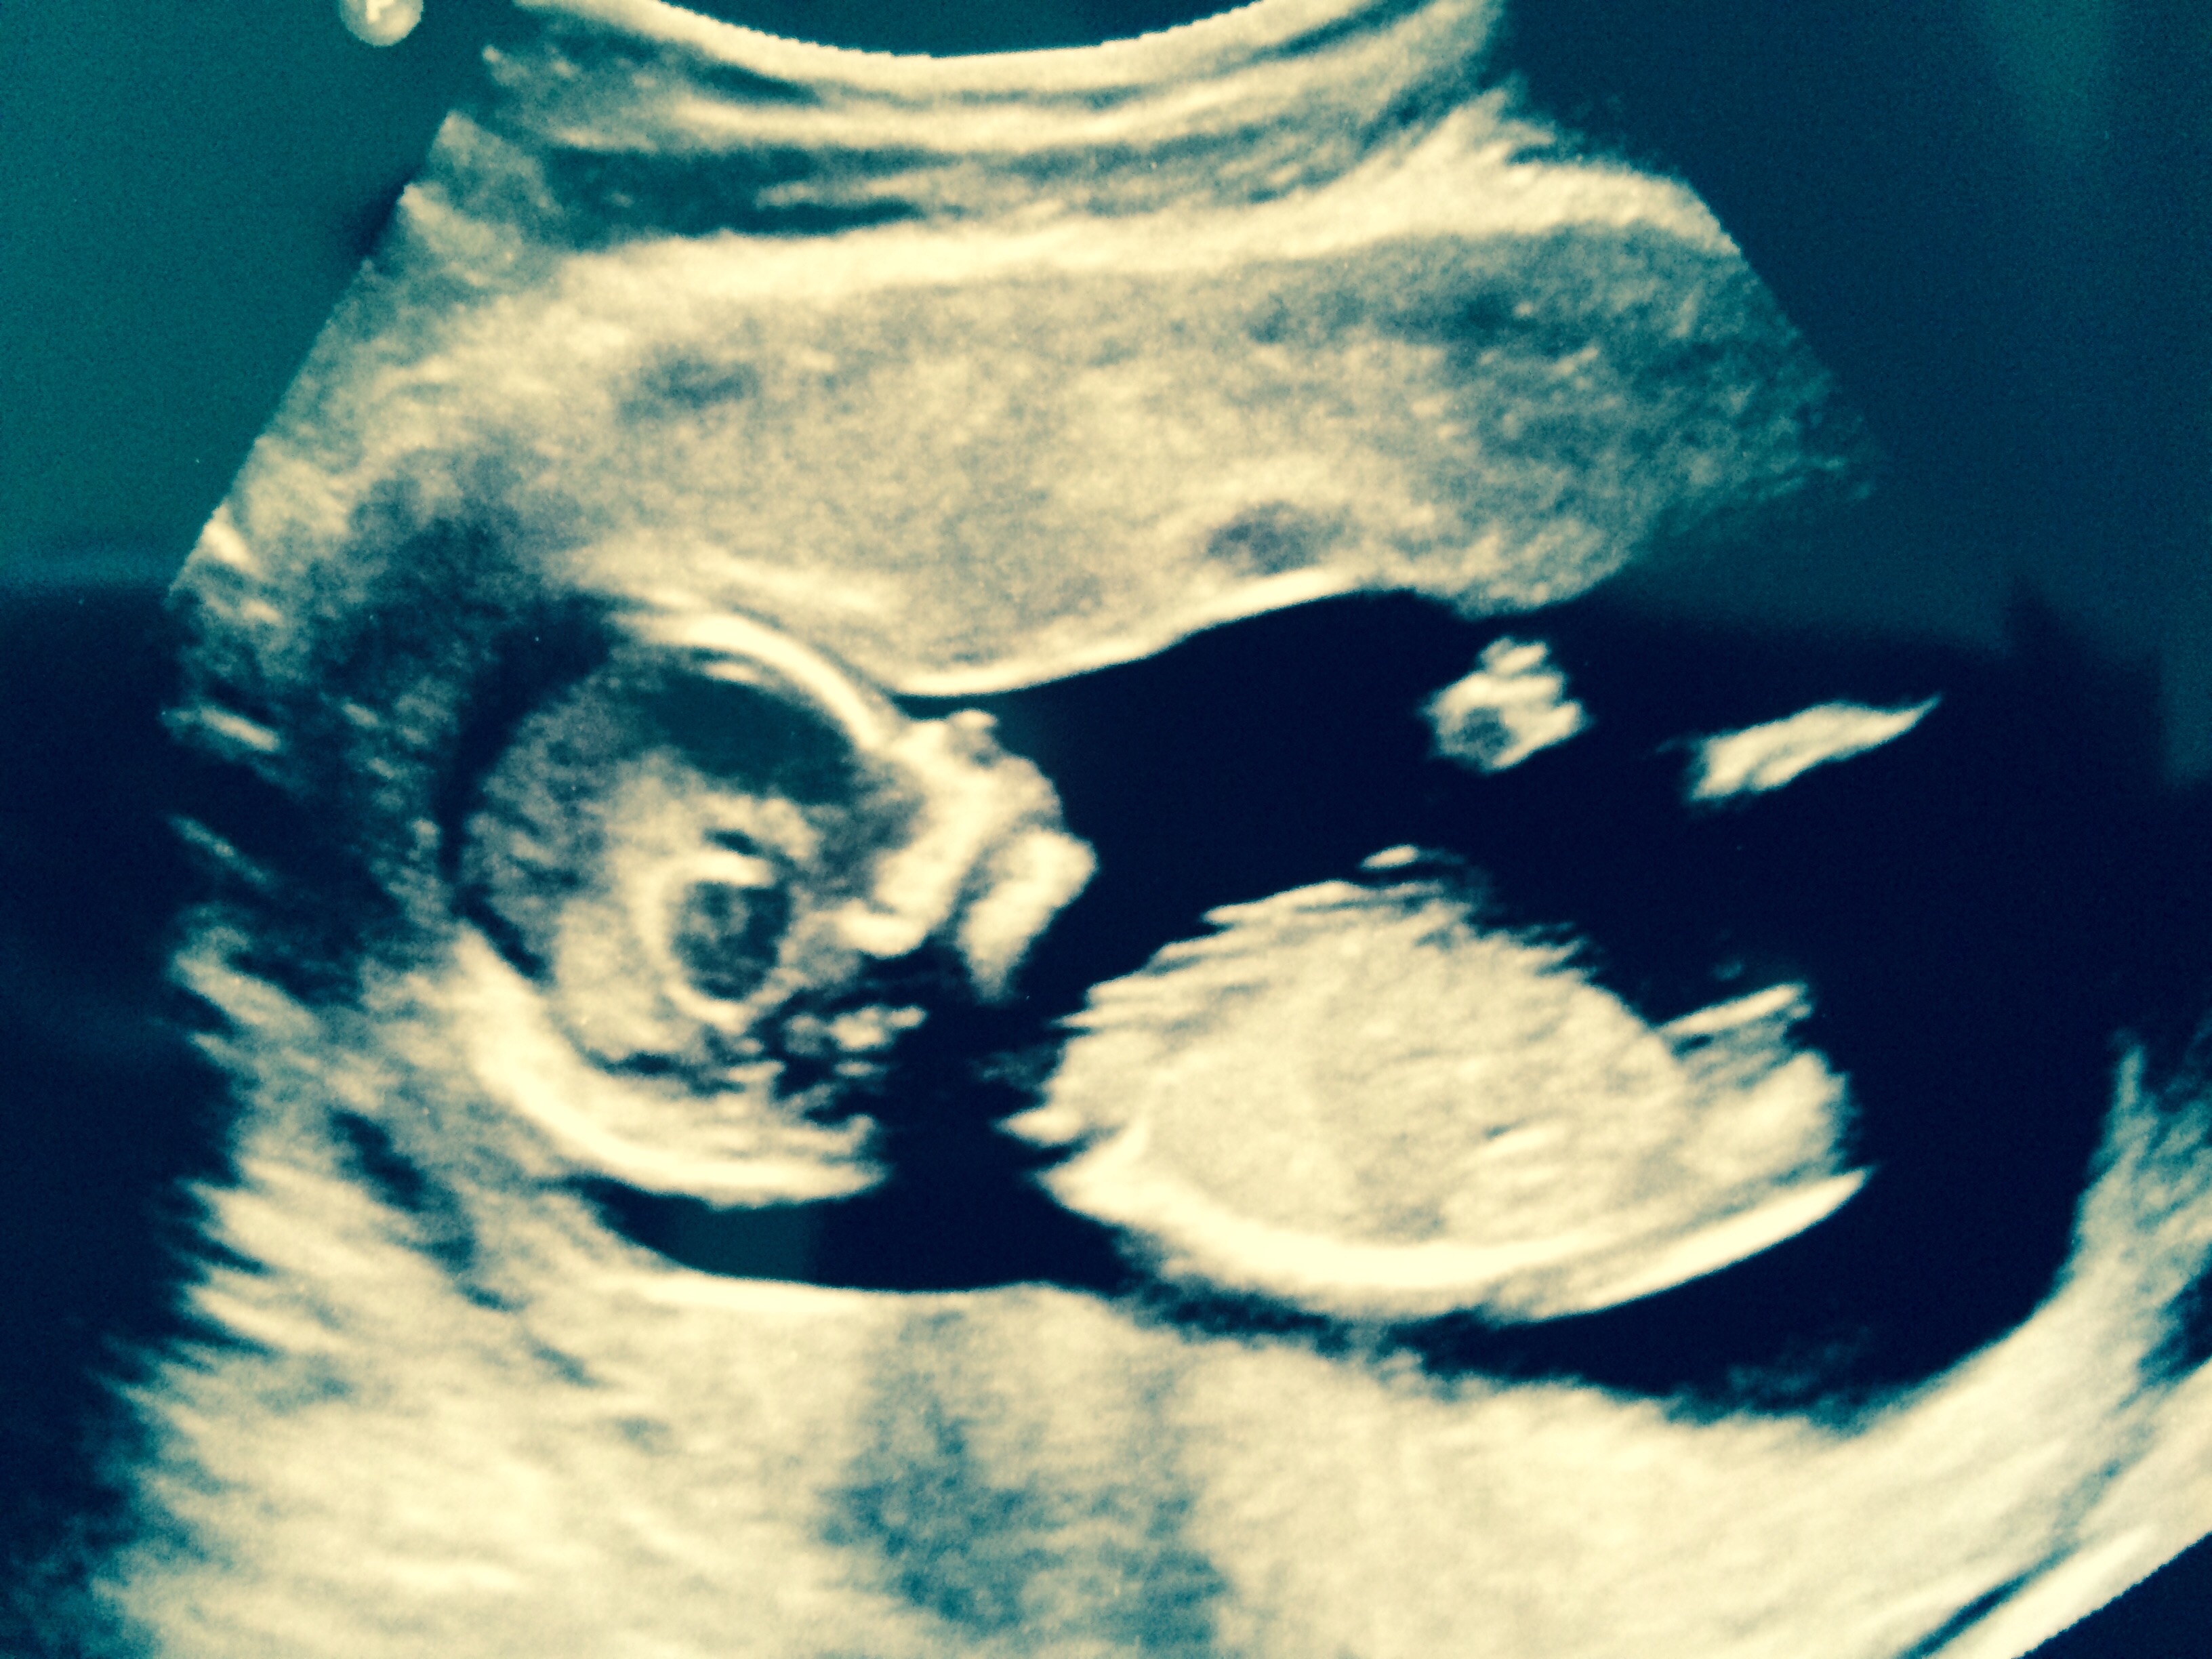

Attachment 27346

I am 12+6 and was measuring 14 weeks! Not sure why this baby is a giant. I might have to lay off all the carbs lol. I'm finding it so hard to be subjective on my own scan. One min I'm a little bit excited and next min back down to reality. Everything has me thinking boy and I totally expected to see a classic little guys nub. Anyway what do you all think of this?